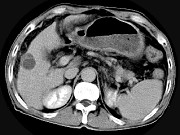

- 单项选择题男,63岁, 肝区疼痛不适1个月,皮肤巩膜无黄染, AFP高于正常,CT所见如图, 最可能的诊断为 ( )